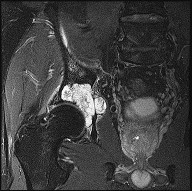

This patient has a dedifferentiated liposarcoma within a preexisting atypical lipomatous tumor. The imaging demonstrates a large fatty mass with increased internal septations proximally (the atypical lipomatous tumor) and a solid enhancing mass distally (the dedifferentiated portion). A biopsy reveals a high-grade liposarcoma. The other diagnostic responses do not reflect sarcomatous transformation of the lesion.

Surgical treatment of a high-grade sarcoma involves wide surgical resection. Radiation decreases local recurrence but does not clearly influence overall survival. The role of chemotherapy in high-grade soft-tissue sarcomas remains investigational; there is a modest (8%-15%) associated improvement in overall survival.

Intramuscular lipomas and atypical lipomatous tumors are treated with marginal resection alone. Radiation therapy for soft-tissue sarcomas may be given before or after surgery. When administered before surgery, patients have a higher wound complication rate but better long-term function attributable to lower rates of lymphedema, fibrosis, and contractures.